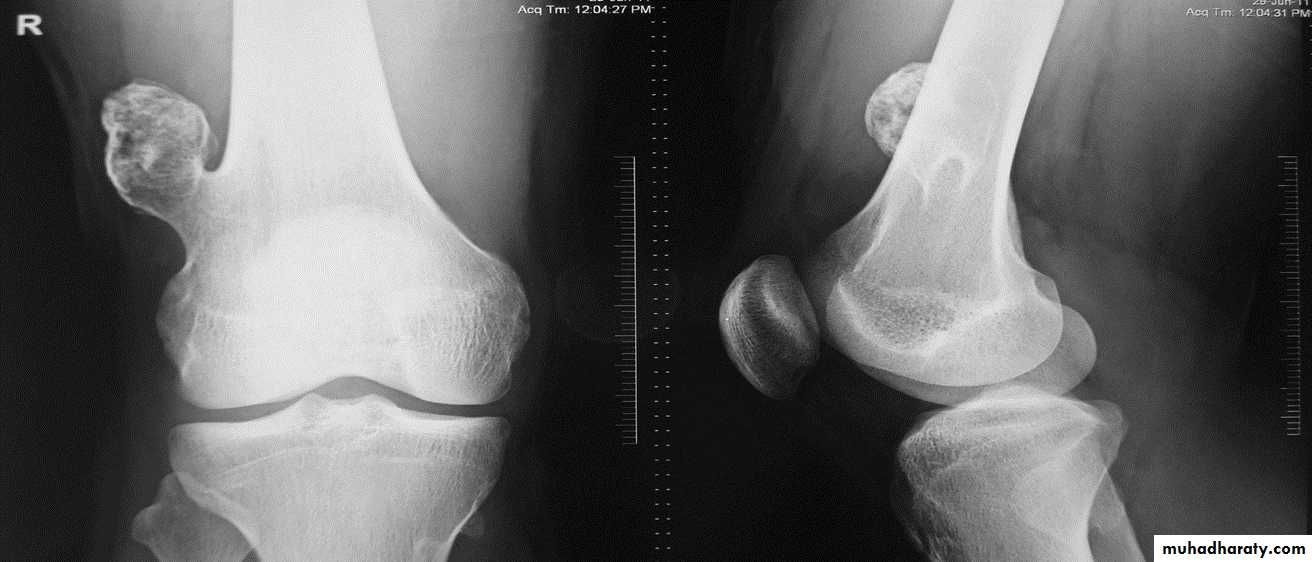

lytic, expansile lesion, Sub articular in location give the soap bubble appearance

*Soap bubble appearance (giant cell tumor )

Q….lytic, expansile lesion, Sub articular in location, Not clearly defined margin with thinning of the cortex ???

Giant cell tumor